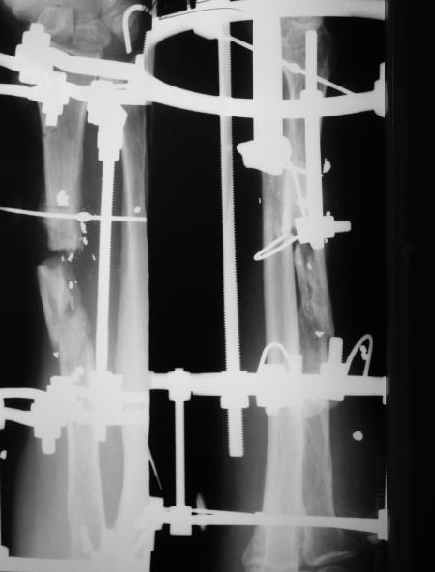

Пока мы наложили аппарат для восстановления оси и длины лучевой кости. Снимок прлагаю.

Снимок сделан после выбирания люфта в аппарате, то есть уже создано приличное дистракционное усилие. Даже пытаться дальше рвать одномоментно не стали.

Спасибо за присланную рентгенограмму после операции. На мой взгляд, было бы неплохо провести еще одну или даже две спицы с упором через промежуточный отломок с противоположной к введенной через дистальный отломок спице с упором.

И все-таки, для интрамемедуллярного стержня во вращающейся лучевой кости потребуется длительная внешняя фиксация. Идти заведомо на "эндопротезирование" лучевой кости, на несращение -- стоило ли огород городить?